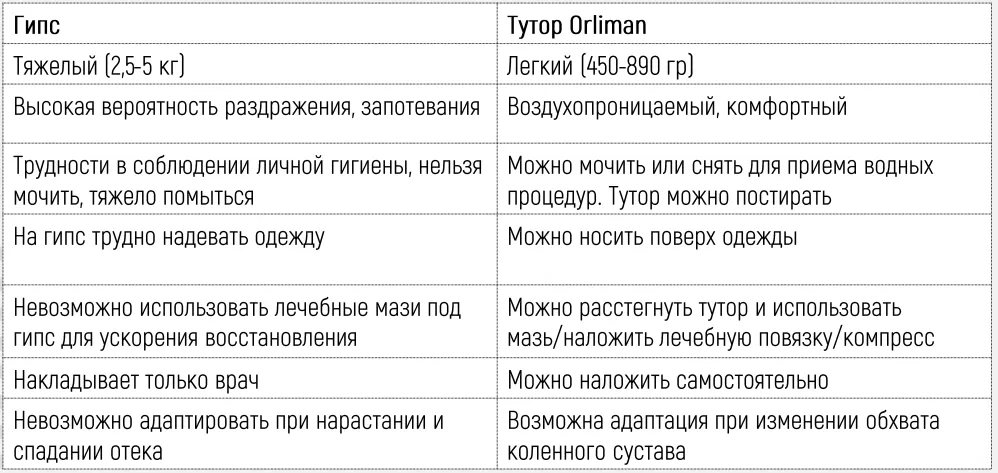

- Альтернатива гипсовой повязке.